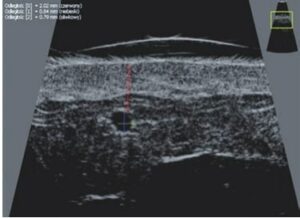

La sonographie Doppler permet l’imagerie des gros vaisseaux et des perforantes qui sont généralement situés dans les couches plus profondes du tissu sous-cutané (fig. 1). Malheureusement, la sonographie conventionnelle n’est pas capable d’imager les vaisseaux plus petits. Afin de visualiser les vaisseaux plus petits situés près de la surface de l’épiderme et dans la couche supérieure du tissu sous-cutané, l’EHF est utilisée (fig. 1). Grâce à l’utilisation de transducteurs dont les fréquences sont supérieures à 20 MHz, une image échographique à haute résolution est obtenue dans laquelle nous pouvons différencier des structures qui sont plus petites que 0,1 mm. Cependant, plus la résolution est élevée, moins la pénétration du faisceau ultrasonore dans les couches de la peau est profonde. Par conséquent, selon le transducteur et l’appareil, il est possible de pénétrer la peau jusqu’à une profondeur maximale de 20–30 mm. Une telle pénétration, associée à une haute résolution d’image, permet l’évaluation de vaisseaux sanguins même très petits (fig. 2). Pendant l’examen avec l’utilisation de transducteurs à haute fréquence, on peut évaluer avec précision le trajet et l’emplacement des petits vaisseaux dans la peau. Cela est particulièrement pertinent pour la sélection de la méthode de fermeture des vaisseaux et la planification de la procédure, car en pratique, la surface de la peau ne montre très souvent qu’un petit nombre de vaisseaux ou un léger fragment de vaisseau – ce n’est qu’après l’examen US que nous pouvons déterminer leur nombre réel et leur trajet. Pour une fermeture efficace du vaisseau, il est nécessaire de le faire sur toute sa longueur. Elle ne doit pas se limiter au fragment vu « à l’œil nu » à la surface de la peau, car la fermeture du fragment entraînera sa recanalisation rapide(7). Fréquemment, le vaisseau visible à la surface de la peau change de trajet, devient plus tortueux et se déplace vers les couches plus profondes de la peau(8). Par conséquent, le trajet de la veine et des perforantes doit être bien connu et déterminé avant la procédure. L’EHF permet également l’imagerie des perforantes entre les petits vaisseaux. De plus, outre l’évaluation du trajet et de l’anatomie, l’image échographique, grâce au logiciel d’échographie, permet également de déterminer les paramètres de base tels que le diamètre du vaisseau, l’épaisseur de sa paroi, la profondeur dans la peau ainsi que la présence ou l’absence de perfusion à l’intérieur du vaisseau(6) (fig. 3). Grâce au transducteur électronique multi-éléments d’une fréquence de 40 MHz introduit sur le marché par Ultrasonix, il est également possible de visualiser la perfusion des vaisseaux en mode Doppler couleur (fig. 4).